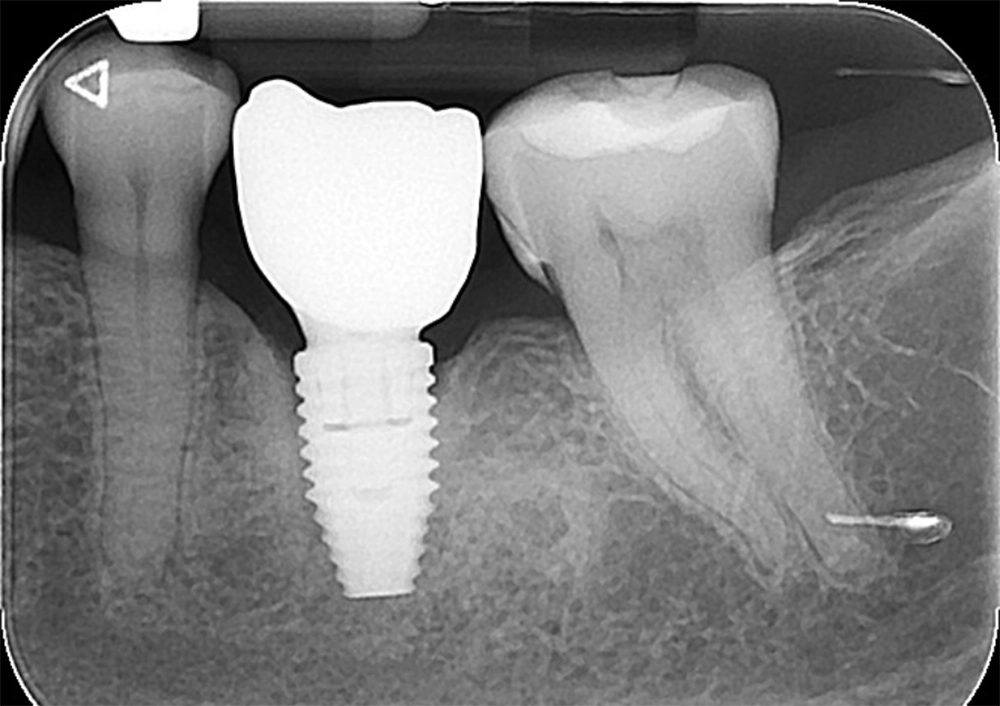

If peri-implant disease develops, a periodontist will assess the condition using techniques like probing, attachment evaluation, and diagnostic X-rays to determine the severity of the infection. Treatment options include:

Surgery may be required for advanced cases or persistent infections. The periodontist will clean the infected area by opening a gingival flap and, if necessary, use a bone graft to regenerate lost bone around the implant.